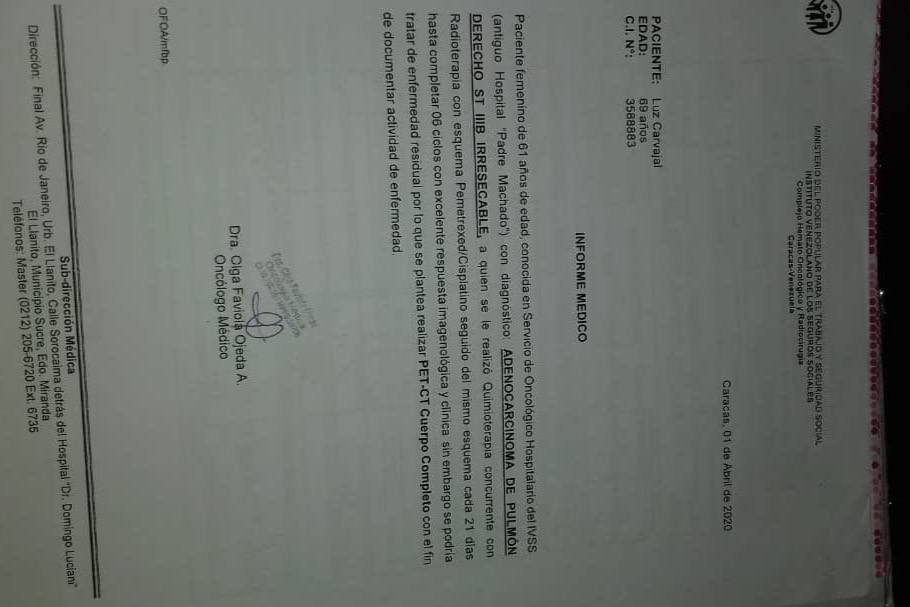

En septiembre de 2019 fue diagnosticada con cáncer de pulmón con una Lesión Ocupante de Espacio (LOE) de 2,5 cm y otra lesión en el Mediastino de 5,4 x 4,7 cm.

A través de varios familiares hemos logrado conseguir dinero para realizarle 36 ciclos de radioterapia y 6 de quimioterapia, además del tratamiento y todos los medicamentos requeridos hasta ahora, logrando una reducción importante del tamaño del tumor en pulmón en 40 %. Gracias a Dios la lesión en el mediastino se redujo también en un 80%.

Sin embargo, aún necesita varios ciclos de quimioterapia adicionales, un examen llamado PET Scan para verificar que no tiene alguna otra célula cancerígena en su cuerpo, una operación para extraer el resto del tumor, y tratamiento para acompañar todo el proceso que podría salvar su vida.

A continuación les dejo el diagnóstico, los exámenes, y los presupuestos de los próximos exámenes que hay que hacerle a mi mamá.

In September 2019, she was diagnosed with lung cancer with a Space Occupying Injury (LOE) of 2.5 cm and another lesion in the Mediastinum of 5.4 x 4.7 cm.

Through several family members we have managed to raise money to perform 36 cycles of radiotherapy and 6 of chemotherapy, in addition to the treatment and all the medications required so far, achieving a significant reduction in the size of the tumor in the lung by 40%. Thank God the injury to the mediastinum was also reduced by 80%.

However, she still needs several additional cycles of chemotherapy, a test called a PET Scan to verify that she doesn't have any other cancer cells in her body, an operation to remove the rest of the tumor, and treatment to accompany the entire process that could save her life. .

Down here I leave the diagnosis, exams, and budgets for the next exams to be done to my mom.